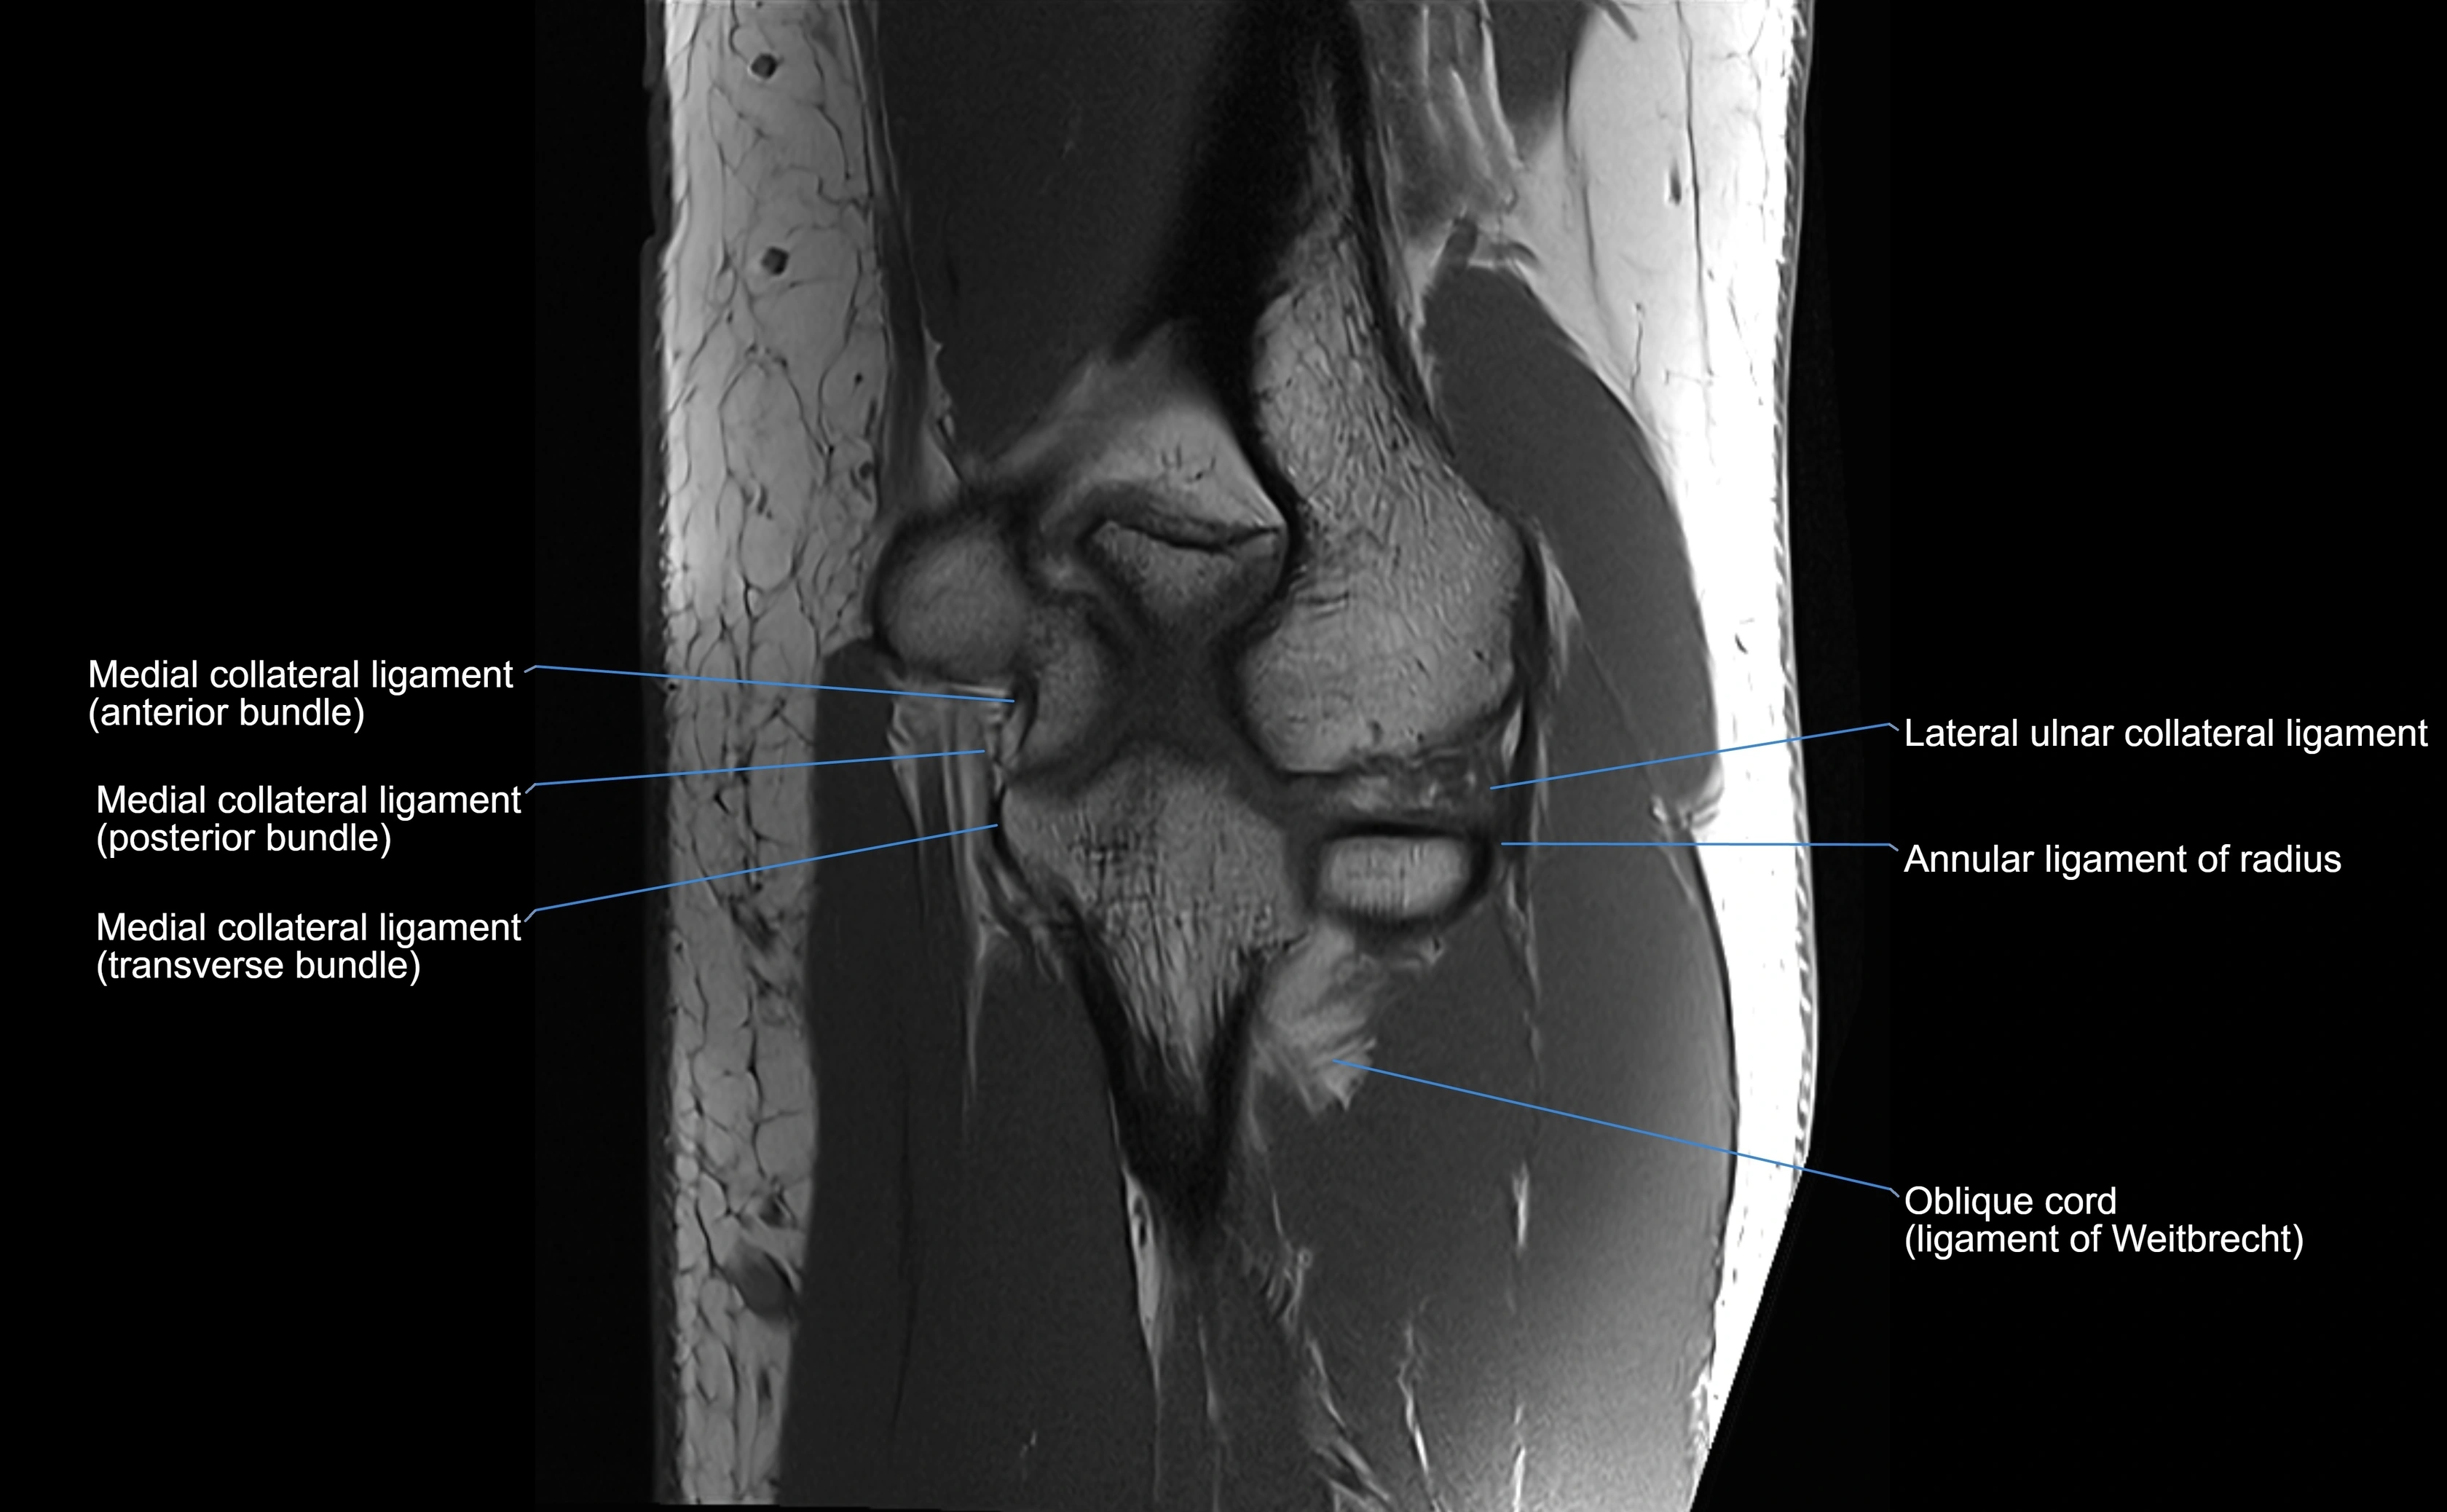

MRI images

image